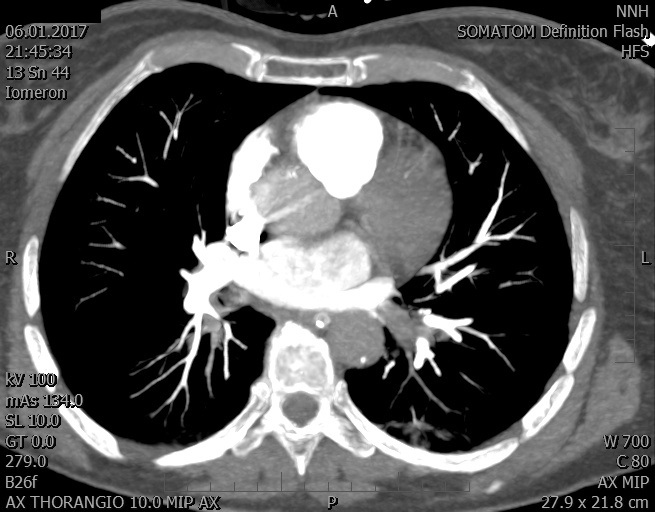

Video 1 - Akutní koronarografie prokázala normální nález na věnčitých tepnách s výjimkou suspekce na lehký spasmus na pravé koronární tepně.Echokardiograficky byla zjištěna těžká dysfunkce dilatované levé komory s nezvětšenou pravou komorou (video 2).

Video 2 - Echokardiograficky byla zjištěna těžká dysfunkce dilatační levé komory s nezvětšenou pravou komorou.Pro nejasnou příčinu zástavy jsme provedli i vyšetření výpočetní tomografií (CT), které vyloučilo plicní embolizaci (série 1 - soubory na konci článku). V den přijetí při přetrvávající oběhové nestabilitě byla nemocná opakovaně defibrilována pro fibrilaci komor se stabilizací rytmu po podání amiodaronu a mesocainu. Dle hemodynamických měření se jednalo o těžký kombinovaný šok. Vstupní laboratorní vyšetření bylo bez větších pozoruhodností. Posléze jsme doplnili anamnézu od příbuzných a zjistili, že pacientka užila do dvou hodin před srdeční zástavou první tabletu amoxicilinu na lehký respirační infekt. Při nevýtěžnosti vstupních vyšetření a nových anamnestických informacích jsme doplnili 14 hodin po kolapsu vyšetření koncentrace tryptázy v séru, která byla extrémně zvýšena (tabulka 2), což nás vedlo k podezření na anafylaxi.